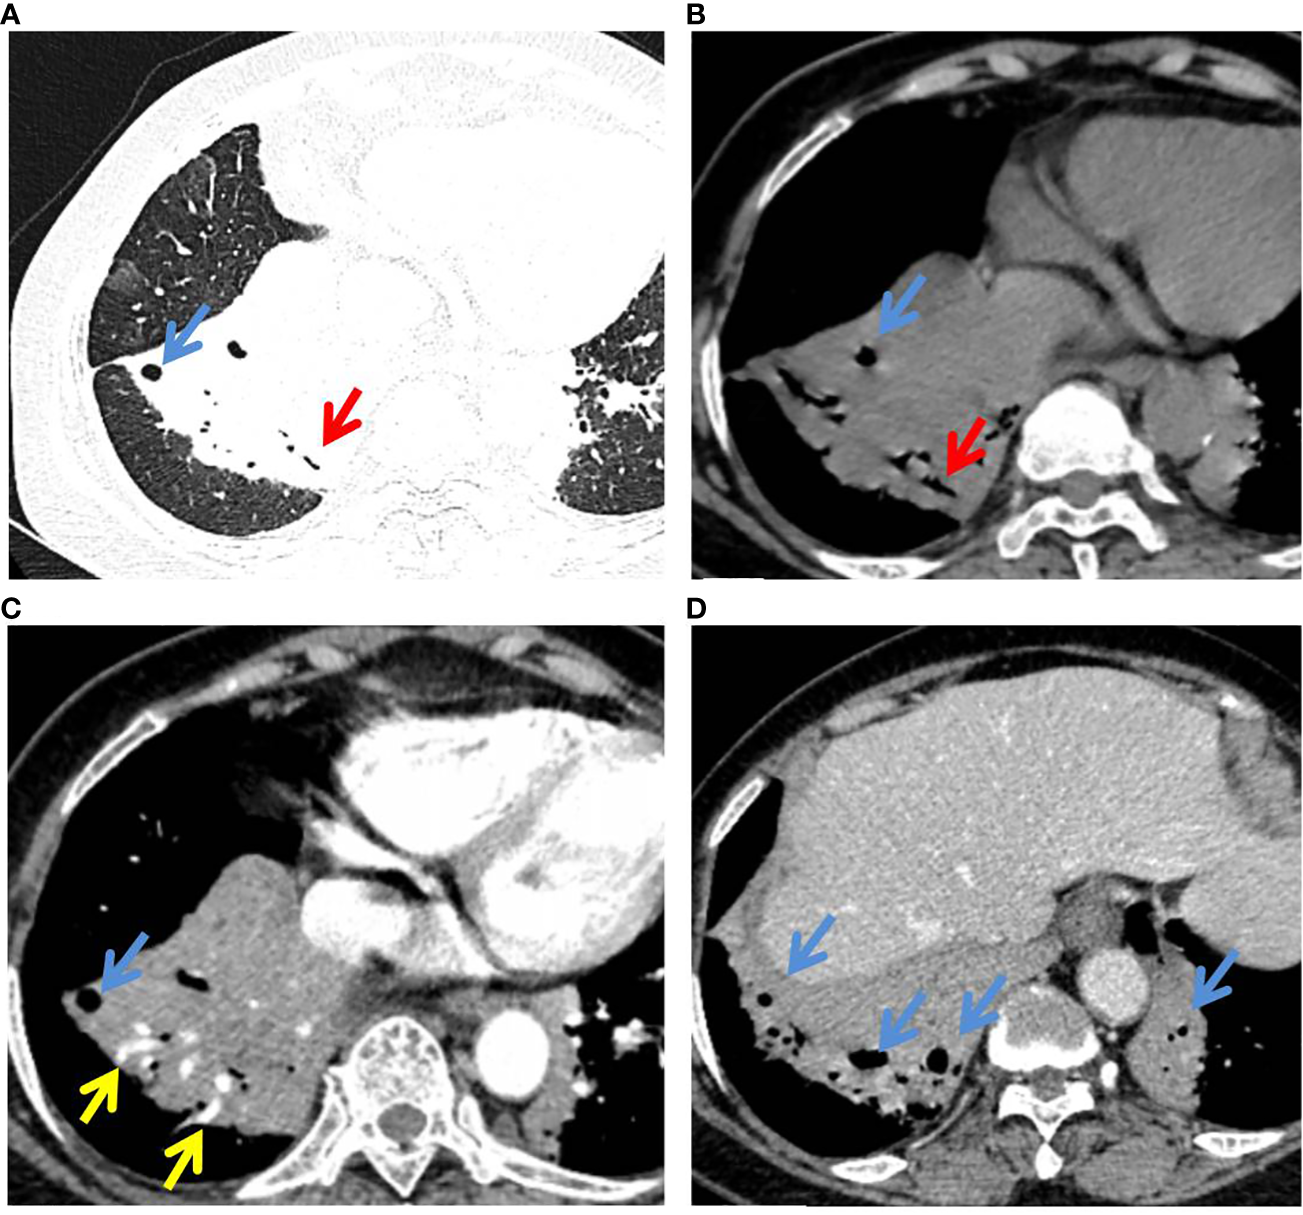

Figure 3

P-MALT lymphoma in a 66-year-old with a cough for 14 days. (A) Axial CT image of the lung window indicated multiple consolidations with air bronchogram (red arrow) and cystic bronchiectasis (blue arrow) in the left lower lobe and right lower lobe. (B–D) Mediastinum-window in the plain scan, arterial phase, and venous phase showed air bronchogram (red arrow), cystic bronchiectasis (blue arrow), and angiogram sign (yellow arrow) within the lesions. CT, computed tomography; C-MALT, consolidation pattern of pulmonary mucosa-associated lymphoid tissue.